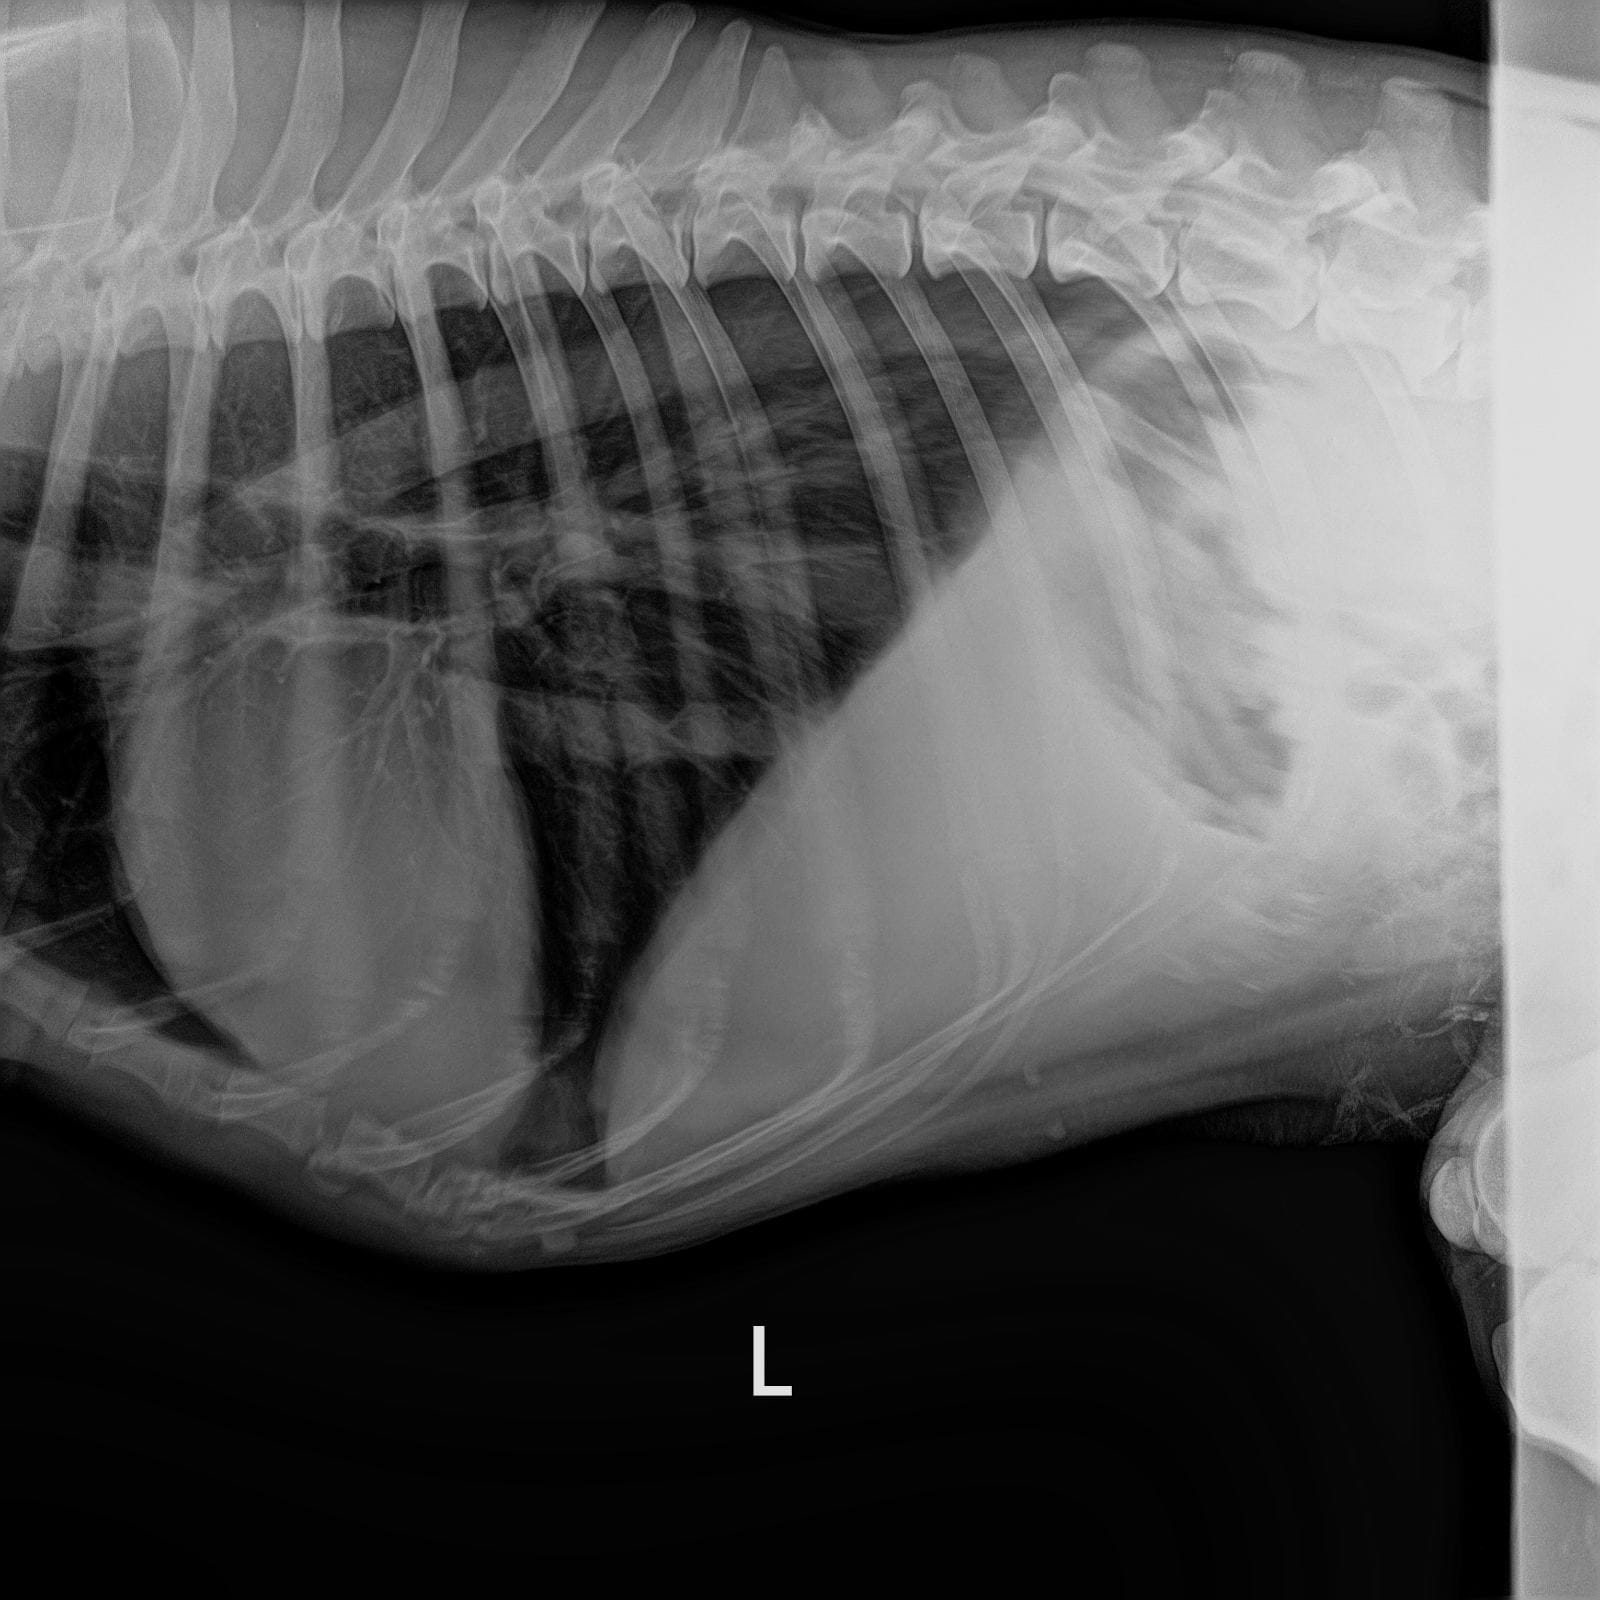

Обследования из клиники Рекс